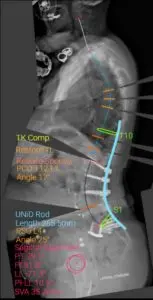

Diagnosis: Proximal junction failure and flat back without a natural lumbar curve

The patient arrived at UVA Health in 2019, two years after her fifth spine surgery, which was completed in Florida.

“Her initial surgeries were for back pain,” says surgeon Xudong Li, MD. “The surgeons started with a fusion of the lower spine and she developed junctional problems. She then had another surgery and another to relieve pain. It’s unusual for someone to have this many surgeries.”

“Her spine was fused almost straight from L1 to S1. She had no natural curvature in her spine, so she was walking leaning forward and she was in a lot of pain,” Li adds. “There was a screw cutting into the bone and a disc was breaking down.”

(Shown above: AP and Lateral Xrays of 74-year-old female after five spine fusion surgeries and SI joint fusion. She has sagittal imbalance and flat lower back with fused spine from L1-S1)